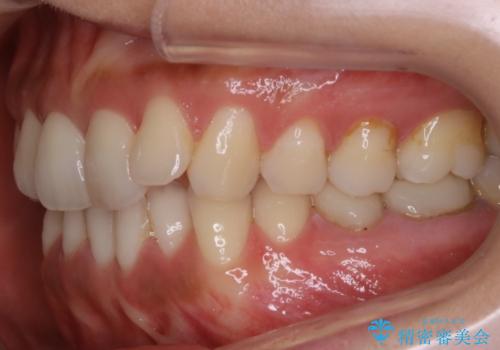

- 歯のガタつきによる見栄えや清掃困難を主訴にご来院されました。

左側の噛み合わせは上の歯が前方に寄ってきてしまっていることが原因のズレがありました。

ガタつき自体は歯列の幅の拡大やディスキング(IPR)でほとんど解消可能でしたが、噛み合わせのズレは歯の移動が必要だったため、左上にマイクロインプラントを使用し噛み合わせの改善とガタつきの解消を同時に進めるという方針をとりました。